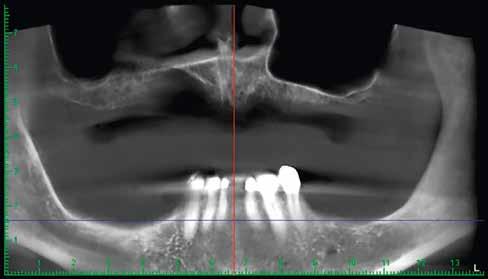

A 75 éves páciens új fogsorokat szeretett volna. Felül nem kielégítő teljes lemezes kivehető fogsora volt, alul pedig szintén nem megfelelő részleges fogsora, néhány devitális, apikális oszteolízist és masszív szekunderkárieszt felmutató mutató maradék frontfogon. Az endodonciai beavatkozást a páciens elutasította. Ehelyett kerámiaimplantátumokra alapozott kezelést kívánt. Az úr általános egészségi állapotában panaszok mutatkoztak. A CMD-index nem volt számottevő. A DVT-vizsgálat (1. kép) alapján megállapítható a 42-es fog decens apikális oszteolízise, számottevő vertikális és horizontális csontveszteség a rágóterületen, valamint az

1. kép: Kiindulási helyzet: az OPG hat devitalizált alsó frontfogat ábrázol, részleges apikális oszteolízissel, szekunderkáriesszel, horizontális csontfelszívódással a rágóterületen.

FDOK/NICO értelmében HU alapján mért erőteljes csontsűrűség-csökkenés mutatkozik az 18, 17, 13, 23, 27 és 28 fogak régiójában.